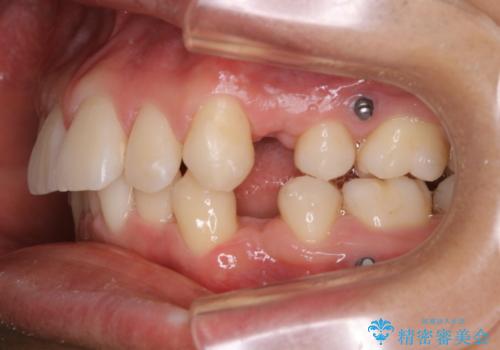

矯正中は汚れが付きやすいため、着色がとても多く付いていました。

抜歯したスペースや装置の周りの磨き方などとても難しため、定期的にクリーニングをおすすめします。